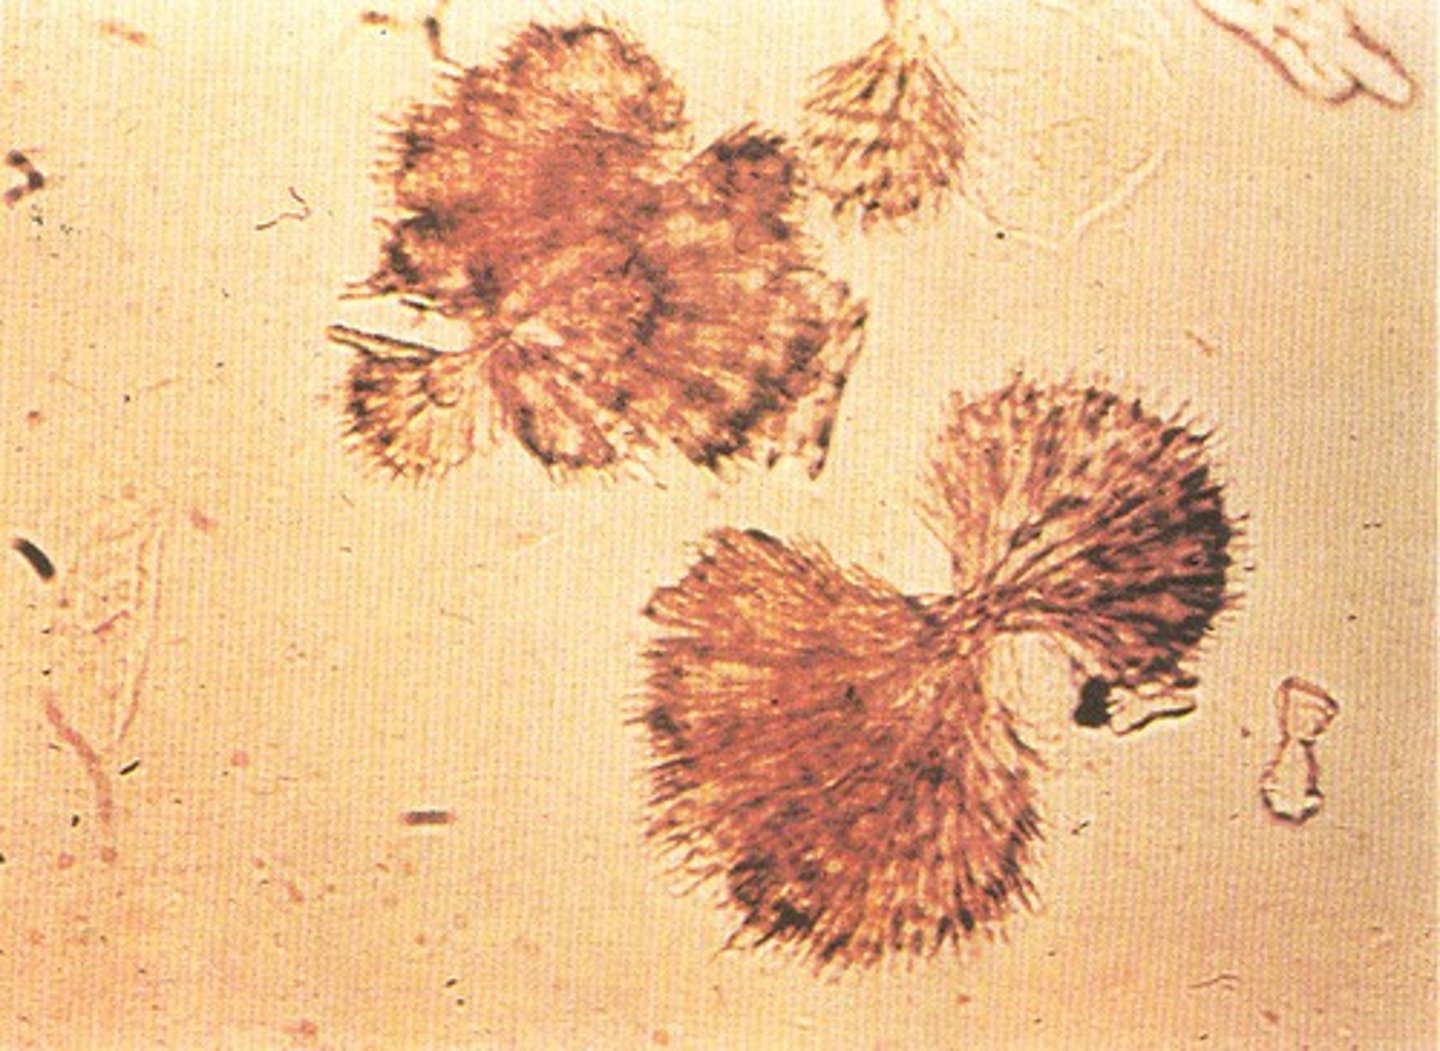

ammonium (bi)urate crystal

urine

round, golden brown in color with irregular spicules